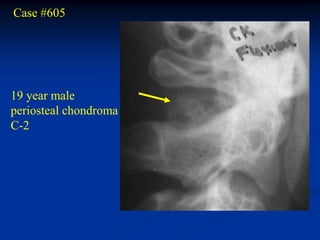

Case #605

19 year male

periosteal chondroma

C-2

Bone scan

CT scan